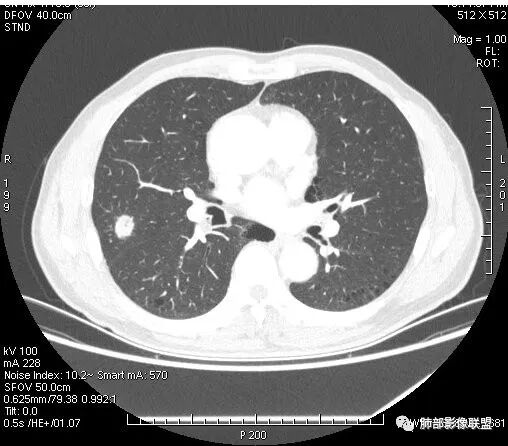

影像学改变:

1.右肺上叶后段类圆形结节影,密度不均,有坏死空洞,坏死比较彻底,内外壁都较清楚。

2.病灶有浅切迹,没有深分叶,毛刺大多细长且柔软。

3.可见棘状突起及胸膜牵拉,但未见胸膜凹陷。

什么意思?结节影有牵拉的动作,但似乎“出工不出力”,收缩力羸弱!

4.病灶轻到中度强化。病灶内血管走行较完好,病灶旁血管局部显示粗大。

5.支气管关系不确定。

6.灶周见小结节影(卫星灶),边界不甚清晰。